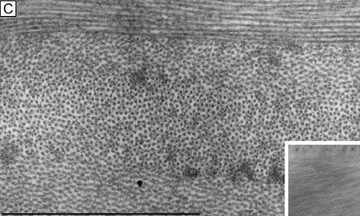

The anterior surface of the human cornea is covered by a transparent, nonkeratinized, stratified (five- to seven-cell layer) squamous epithelium uniformly around 50 μm in thickness that is continuous with the epithelium of the limbus and conjunctiva (Figs. 1, 2, and 3). The basal corneal epithelial cells actively secrete extracellular material (type IV collagen, laminin, heparin, and small amounts of fibronectin and fibrin) that forms an underlying 75-nm thick basement membrane called the basal lamina. On electron microscopy, the morphology of basal lamina appears to be composed of two distinct layers: a 25-nm thick lamina lucida and a 50 nm thick lamina densa (Fig. 3).

Fig. 3. Transmission electron micrograph (3,500×) of the central corneal epithelium with a summary diagram (inset). Microvilli project from the anterior corneal surface into the tear film. S, squamous cells; W, wing cells; B, basal epithelial cells. Bar = 1 μm. (Inset modified from Hogan MJ, et al. Histology of the human eye. Philadelphia, WB Saunders, 1971.)

The cytoplasm of a corneal epithelial cell primarily contains cytoskeletal intermediate filaments and has sparse cytoplasmic organelles (i.e., mitochondria, endoplasmic reticulum, and golgi apparatus). The predominant cytoplasmic filament is keratin, whereas actin and microtubules are two other major types found in corneal epithelial cells. The epithelial cells are held together to one another by numerous anchoring junctions called desmosomes, whereas the basal surface of the epithelium adheres to the basal lamina and underlying Bowman's layer through aa adhesion complex composed of hemidesmosomes, anchoring fibrils (type VII collagen), and anchoring plaques (Fig. 4). The function of the corneal epithelium is twofold: (a) to form a barrier from the environment to the corneal stroma of the cornea, and (b) to form a smooth refractive surface on the cornea through interaction with the tear film.

Fig. 4. Transmission electron micrograph (10,000×) of a basal epithelial cell showing the adhesion complexes (arrowheads) that anchor it in place onto the Bowman's layer and summary inset. B, basal epithelial cell. Bar = 1 μm. (Inset from Albert and Jakobiec: Principles and practice of ophthalmology. Philadelphia, WB Saunders, 2000.)

The epithelial cells differentiate from the basal layer to form two to three cell layers of wing cells and finally to form two to three cell layers of squamous cells (Fig. 3). The squamous cells form a barrier junction because they are surrounded by a continuous encircling band of zonula occludens tight junctions, which serve as a semipermeable, high-resistance (12–16 kΩ cm2) membrane6,7 by closing off the intercellular space. This barrier prevents the movement of fluid from the tears into the stroma and also protects the cornea and intraocular structures from infectious pathogens. The apical surface of the corneal epithelium is specialized to maintain the tear film as microplicae and microvilli on the surface of the most superficial epithelial cells is covered with a glycocalyx and membrane-spanning mucins (MUC 1 and possibly MUC 4); altogether these structures and substances form the 1.0 μm thick mucinous layer of the tear film (Fig. 5).8–10